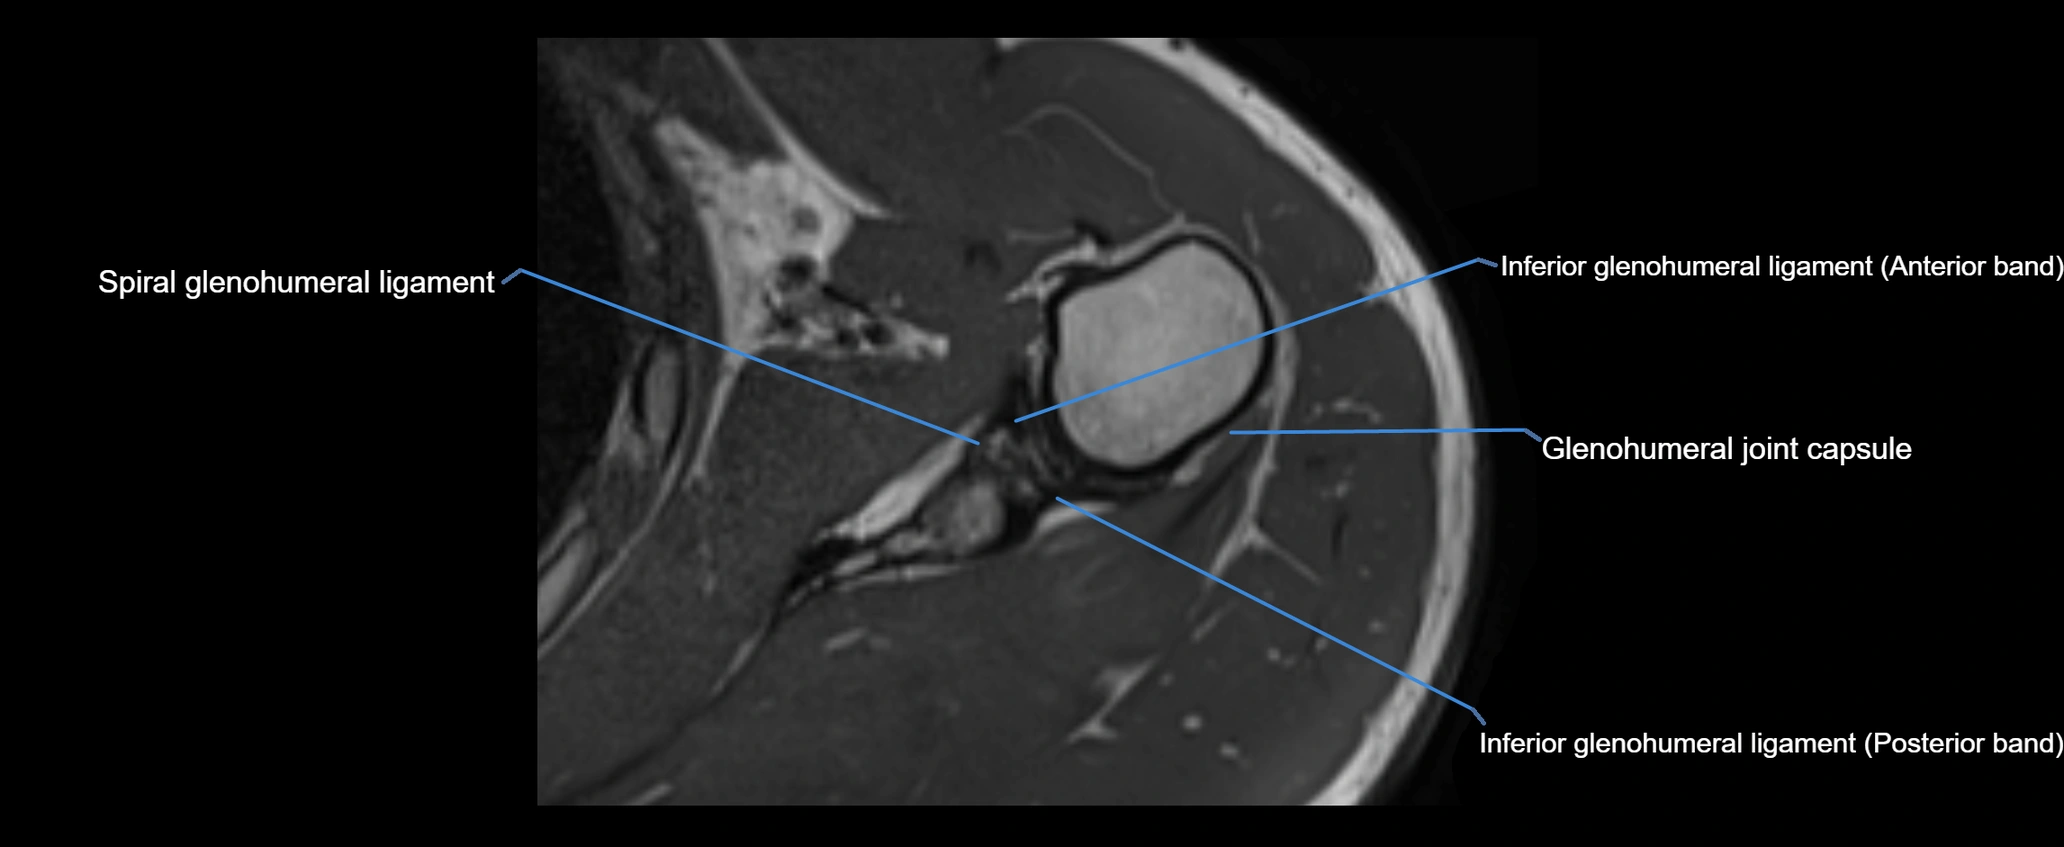

MRI images

image